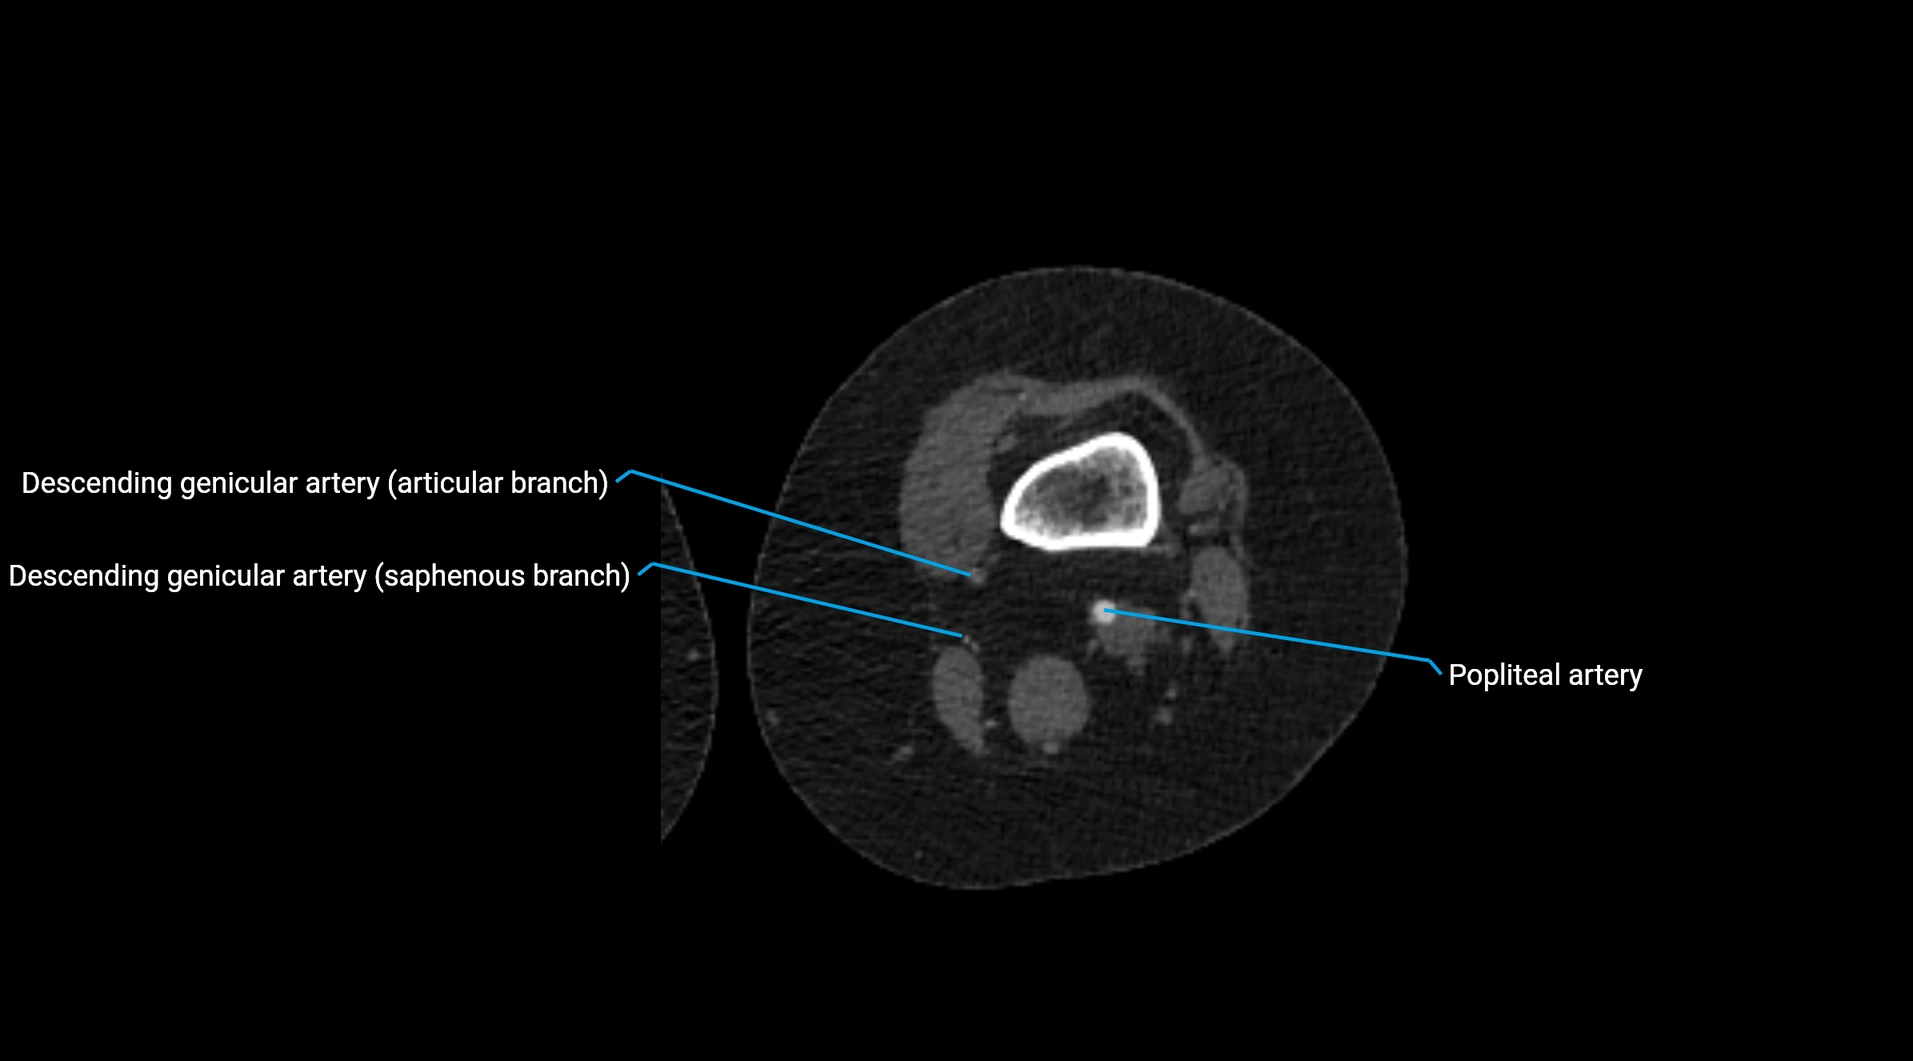

CT images

image